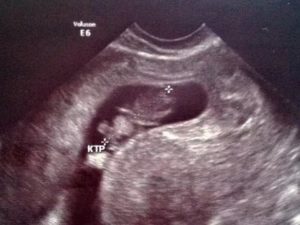

Сегодня ходила на повторное УЗИ, первое делала 10 дней назад, там увидели плодное яйцо 5 мм и сказали, что всё хорошо. Моя Г считает, что УЗИ не вредно, но очень информативно — я с ней согласилась, поэтому решено было сделать ещё одно УЗИ для контроля.

На втором УЗИ увидели уже бусинку внутри плодного яйца, увидели пульсацию сердца, но ещё увидели гипертонус матки. Г и врач УЗИ не стали меня сильно пугать, старались успокоить, но предупредили об угрозе выкидыша. Я уже более двух недель пью Магне B6 и обычный набор витаминов.